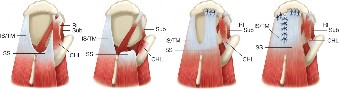

The correct answer is (A). Massive and immobile tears can be either U-shaped or longitudinal. These can sometimes be repaired using an anterior or posterior

interval slide technique. In an anterior interval slide technique, there is some anterior portion of the supraspinatus still attached to the greater tuberosity laterally and rotator interval anteriorly. The greater tuberosity attachment can be incised and the rotator interval attachment can be detached by incising the coracohumeral ligament. In a posterior interval slide technique, there is some posterior portion of the supraspinatus still attached to the infraspinatus. This can be detached by incising the interval between the supraspinatus and infraspinatus (Answer B). These interval slide techniques decrease the tension and improve lateral mobilization, allowing the supraspinatus to be more easily repaired to the greater tuberosity. The posterior leaf of the tear is then brought together with the anterior leaf through marginal convergence, leaving you with a small crescent-shaped tear that can be repaired to the greater tuberosity (see Fig. 2–16).

Figure 2–16_Massive, immobile rotator cuff tear and repair using anterior interval slide followed by marginal convergence. SS, supraspinatus; IS/TM, infraspinatus/teres minor; RI, rotator interval; CHL, coracohumeral ligament; Sub, subscapularis. (Redrawn from Burkhart SS, Lo IKY. Arthroscopic rotator cuff repair. J _Am Acad Orthop Surg. 2006;14(6):333–346.)

Crescent-shaped tears are not retracted much medially, can be mobilized laterally relatively easily, and thus can be relatively easily repaired to humeral bone (see Fig. 2–13).

Figure 2–13_Crescent-shaped rotator cuff tear and repair. SS, supraspinatus; IS, infraspinatus. (Redrawn from Burkhart SS, Lo IKY. Arthroscopic rotator cuff repair. _J Am Acad Orthop Surg. 2006;14(6):333–346.)

U-shaped tears can be repaired using marginal convergence (Answer E). U-

shaped tears have an apex that extends further medially, usually to the edge of the glenoid in the sagittal plane, and this part cannot be mobilized all the way to the greater tuberosity. Because of this lack of mobility, these tears have to be repaired using marginal convergence, which is essentially zipping up the U from the apex toward the greater tuberosity using side to side sutures to bring together the anterior and posterior leaves of the U-shaped tear. In performing this marginal convergence, you essentially are converting a U-shaped tear into a crescent-shaped tear that can be relatively easily mobilized to the greater tuberosity, allowing it to be repaired (see Fig. 2–14).

Figure 2–14_U-shaped rotator cuff tear and repair using marginal convergence. SS, supraspinatus; IS, infraspinatus. (Redrawn from Burkhart SS, Lo IKY. Arthroscopic rotator cuff repair. _J Am Acad Orthop Surg. 2006;14(6):333–346.)

Finally, an L-shaped tear resembles a tear that can be thought of as partially a crescent-shaped tear and partially a U-shaped tear. One leg of the L is the more mobile, less retracted, crescent-shaped tear which transitions into the other leg of the L, a less mobile, more retracted part of the tear which mechanically and visually resembles a U-shaped tear. The retracted U-shaped part, like a normal U-shaped tear, must be repaired using marginal convergence. Then the remaining crescent-shaped part, like a normal crescent-shaped tear, can be mobilized laterally and repaired to bone (see Fig. 2–15).

Figure 2–15_L-shaped rotator cuff tear and repair using marginal convergence. SS, supraspinatus; IS, infraspinatus; RI, rotator interval; CHL, coracohumeral ligament; Sub, subscapularis. (Redrawn from Burkhart SS, Lo IKY. Arthroscopic rotator cuff repair. _J Am Acad Orthop Surg. 2006;14(6):333–346.)